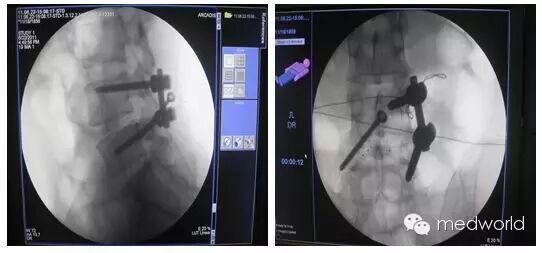

北京中诺恒康生物科技有限公司研发生产的脊柱手术通道系统为一次性使用通道耗材,国内独家上市产品,该通道能通过一个小切口(62.5px)经肌肉间隙提供从椎弓根到椎弓根的暴露,在此空间内能完成椎间隙的减压、固定和融合。

此通道系统采用椎旁入路,能明显减少对肌肉的挤压。肌肉的功能保留和良好康复效果成为减少远期腰椎术后失败综合征的重要解剖稳定基础。完成手术所需皮肤切口仅为一枚硬币大小。